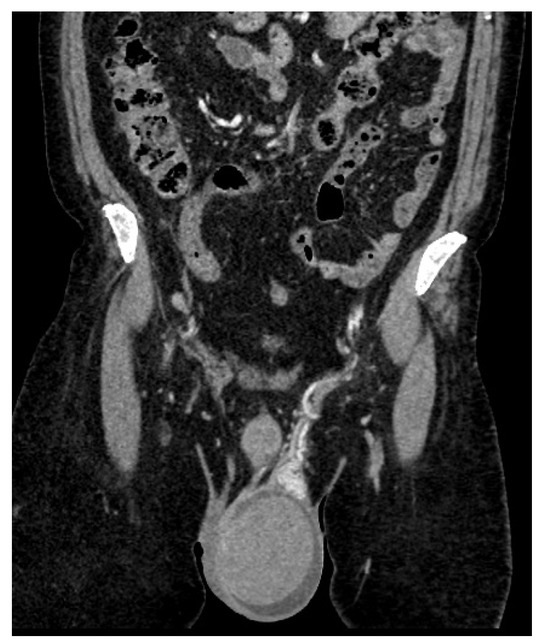

| June 2022 | first extramedullary relapse left testicular—diagnostic immunophenotyping of semen | HyperCVAD Block A radiotherapy, 24 gy/12 sessions for the scrotal sac and the lymph nodes along the left spermatic vein result: complete metabolic remission petct |